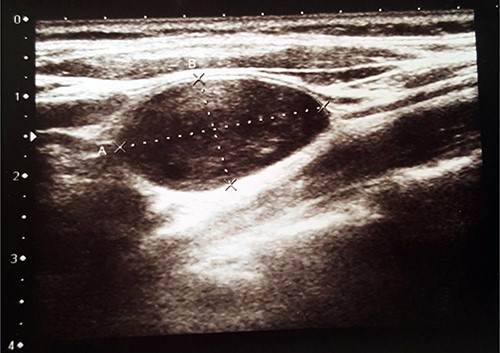

Histopathological examination revealed typical features of schwannoma (Figs 2 and 3). Tumour was well demarcated, encapsulated, composed of spindle cells, organized in a palisading fashion and had hypocellular myxoid component with large vessels. Tumour cells had an ill-defined cytoplasm and elongated nucleus. There was no mitotic activity.

Biphasic tumour: compact hypercellular Antoni A area (right) and myxoid hypocellular Antoni B area (left).

Macroscopically schwannoma looks like yellowish-white, well-circumscribed mass [1, 6]. Microscopically, the baseline features of schwannoma are Antoni type A tissue and Antoni type B tissue [1, 4]. Necrosis, haemorrhage and cystic degeneration are other specific features [1, 4].